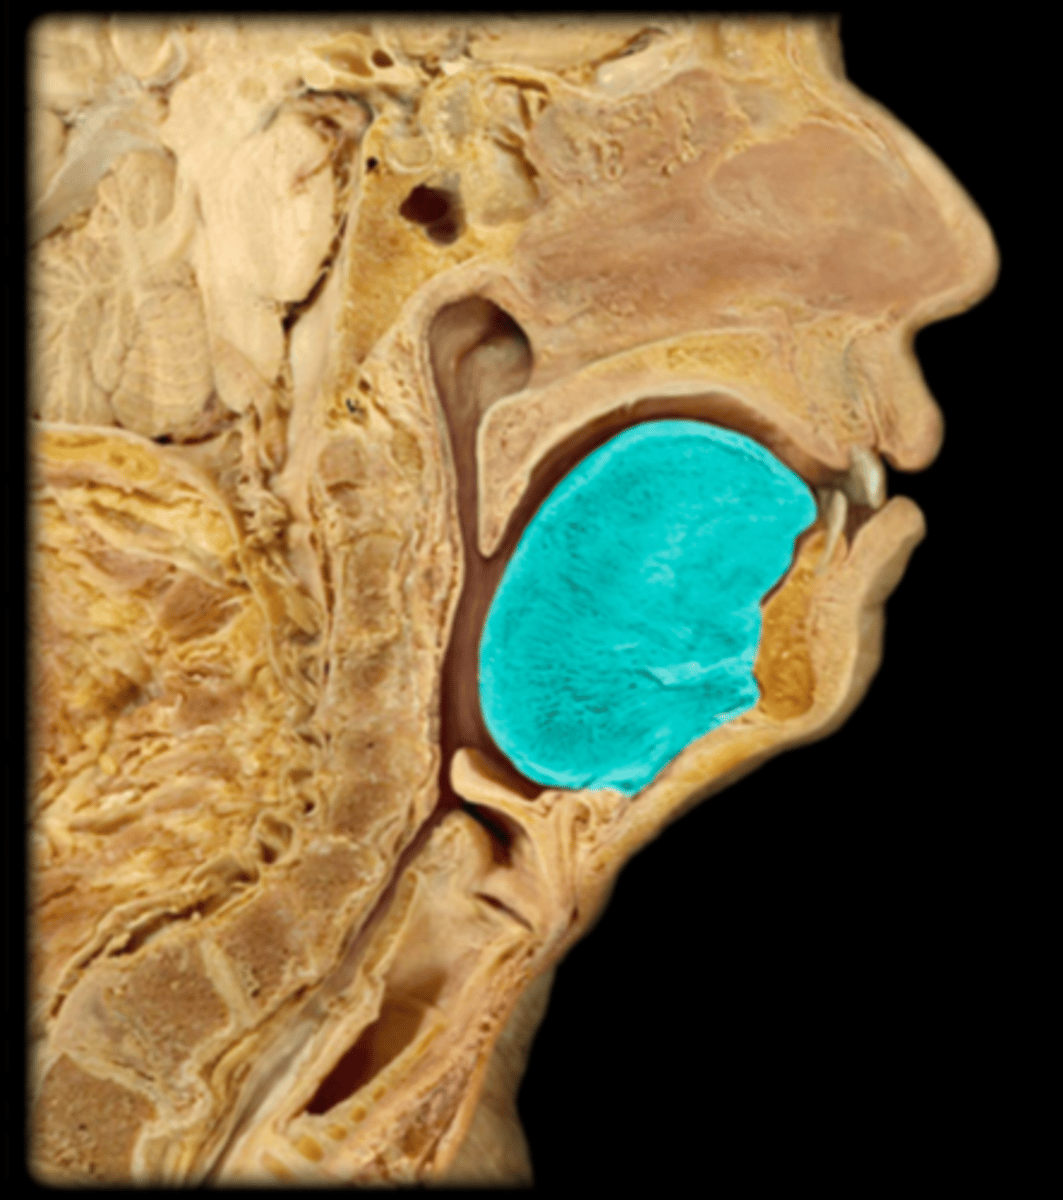

Tongue

Lingual Tonsil

Palatine Tonsil